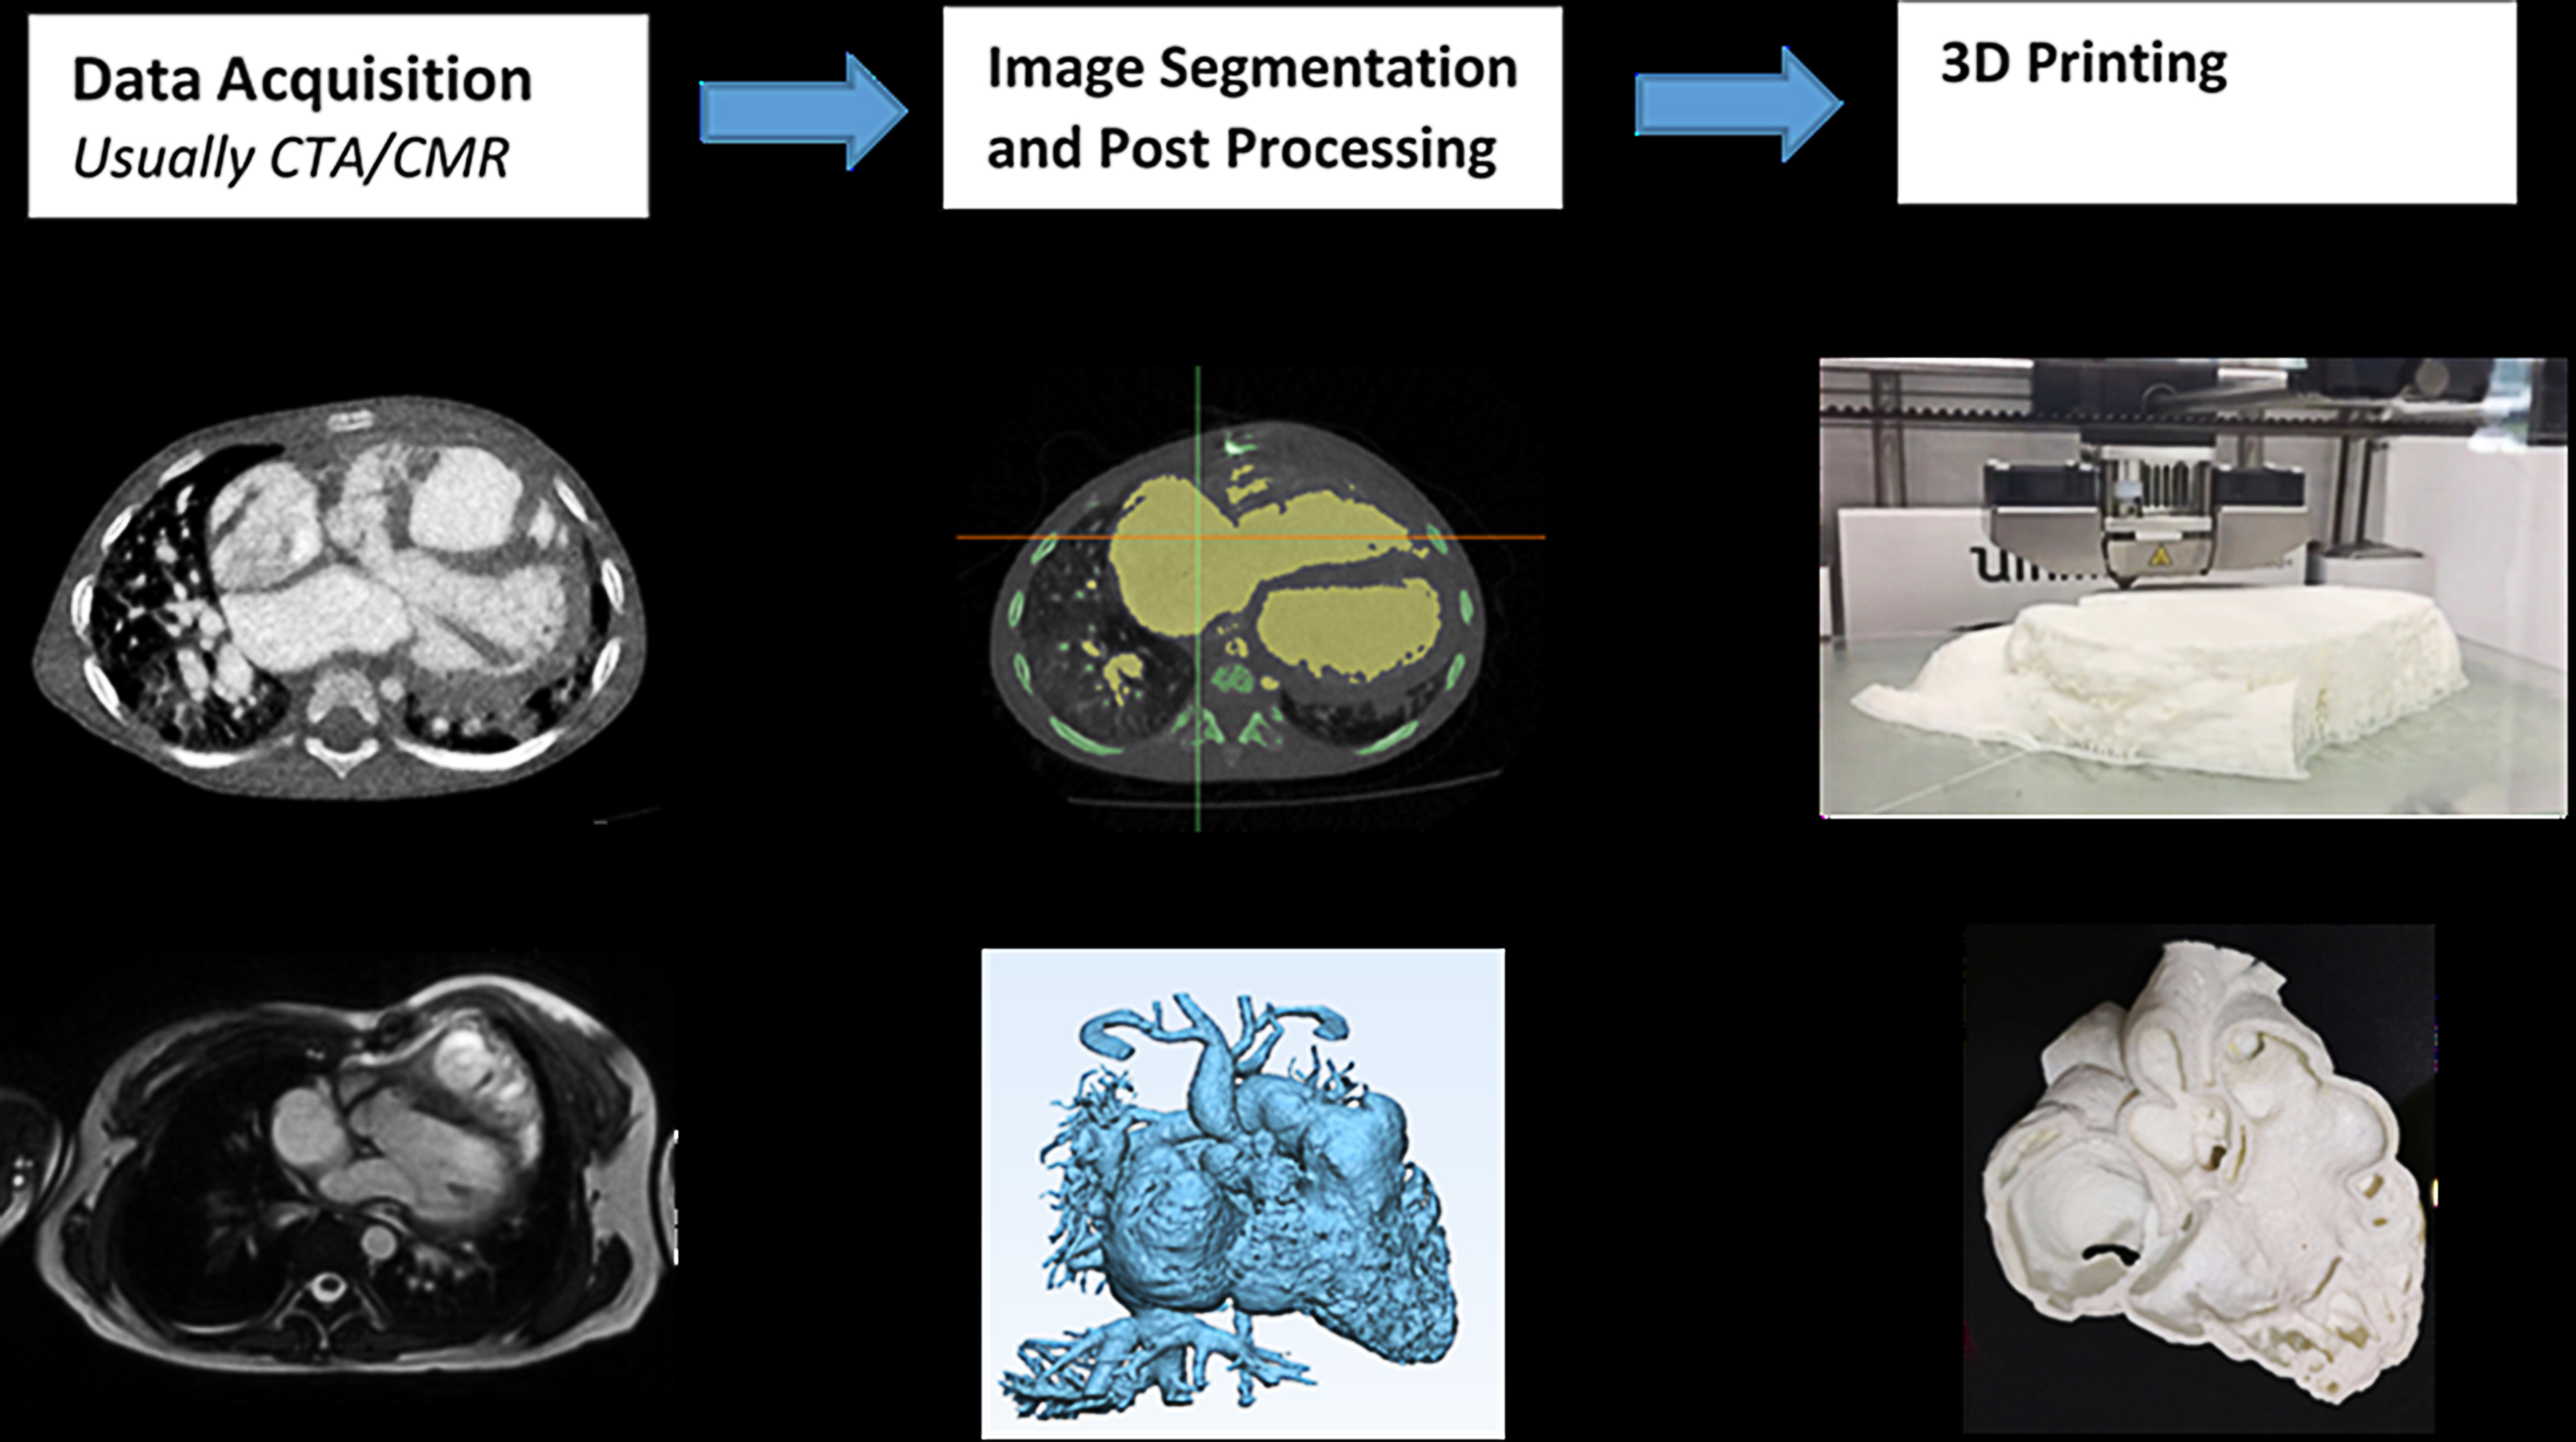

The first step to generate the 3DPHM was to convert the CCTA images into printable digital model in standard tessellation language (STL) format using Mimics Innovation Suite 22.0 (Materialise HQ, Leuven, Belgium) (Fig. 1). The details of the conversion process were elucidated previously [12, 13]. The required time for this conversion process was 45 minutes on average, however it was highly dependent on the image quality of the source data. Following that, the STL files were sent to the 3D printers for printing (Fig. 1, Ref. [14]).

Fig. 1.

Fig. 1.Conversion of CCTA into printable STL files. CTA, computed tomography angiography; CMR, cardiac magnetic resonance; 3D, three-dimensional. Reprint with permission under the open access from Sun et al. [14].